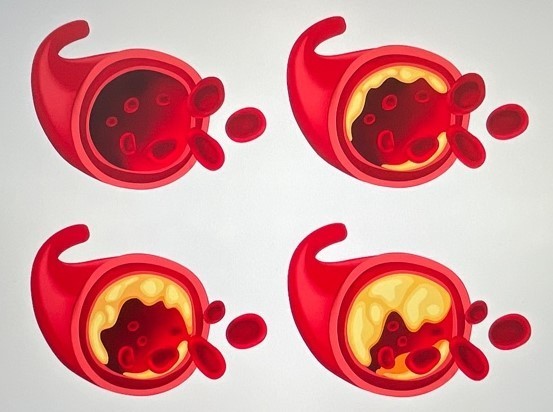

고지혈증 증상 10. 심근경색 또는 뇌졸중 위험 증가

고지혈증을 방치하면, 혈관 속에 플라크가 쌓이고,

이것이 혈전을 만들어 혈관을 막아버릴 수 있어요.

결과적으로 심근경색, 뇌졸중(뇌경색) 같은 치명적 질환으로 이어질 수 있습니다.

이런 상태에 이르기 전에 관리가 꼭 필요합니다.고지혈증 주의사항